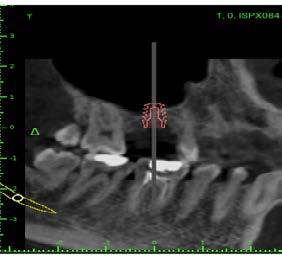

La oseodensificación constituye una técnica innovadora en cirugía implantológica, pues permite la optimización de los resultados en la colocación de implantes dentales y en procedimientos regenerativos como la elevación sinusal transcrestal.1 Este artículo presenta un caso clínico que ejemplifica su aplicación dentro del protocolo quirúrgico de elevación sinusal transcrestal para la colocación de un implante dental endoóseo. Su finalidad es evaluar la eficacia de la oseodensificación en la elevación sinusal transcrestal y osteotomía, para mejorar la estabilidad primaria y la integración ósea en la colocación de implantes dentales endoóseos. Paciente femenina de

40 años acudió para la rehabilitación del sector posterior superior, pues presentaba un defecto vertical en el cuadrante superior derecho a la altura del primer molar, una altura óseorresidual de 3.5 mm y un tipo óseo III. Dadas las condiciones, se optó por la técnica de oseodensificación para la elevación del piso del seno maxilar y la preparación del lecho implantario. Entre los hallazgos descritos en los resultados se encontró una elevación sinusal de al menos 6 mm, evidenciada en las imágenes radiográficas intraoperartorias, que permitió la colocación de un implante de 5 mm de plataforma por 8 mm de longitud, ubicado 1 mm en posición subcrestal. Una tomografía

axial computarizada confirmó la situación del implante, así como la efectividad de la oseodensificación y la elevación del piso sinusal de 6 mm. la osteointegración del implante se completó sin necesidad de procedimientos quirúrgicos adicionales de mayor complejidad. Se concluye que la oseodensificación es una técnica eficaz y predecible para la osteotomía y la elevación sinusal transcrestal, favorece la estabilidad primaria del implante y constituye un procedimiento mínimamente invasivo.

Figura 2. Planeación en tomografía axial computarizada: a) vista sagital, b) vista transversal, c) vista 360°, d) reconstrucción 3D y e) ortopantomografía.

Planeación tomográfica

Se creó un mapeo óseo para evaluar las dimensiones de altura y anchura ósea disponibles para la colocación del implante dental y su posterior restauración protésica. El análisis reveló una cantidad reducida de tejido óseo en el piso del seno maxilar (3.61 mm), lo que condicionó la planificación del procedimiento. Para la rehabilitación implantológica, se requiere la colocación de un

implante de al menos 8 mm de altura por 5 mm de diámetro, con adecuado espacio vestíbulo-palatino e interoclusal. No obstante, luego de considerar la insuficiencia de volumen óseo en sentido vertical y el grado de neumatización del seno maxilar, se determinó que la colocación del implante mediante técnicas convencionales no era viable, por ello la necesidad de procedimientos de aumento óseo para lograr una rehabilitación adecuada (Figura 2).